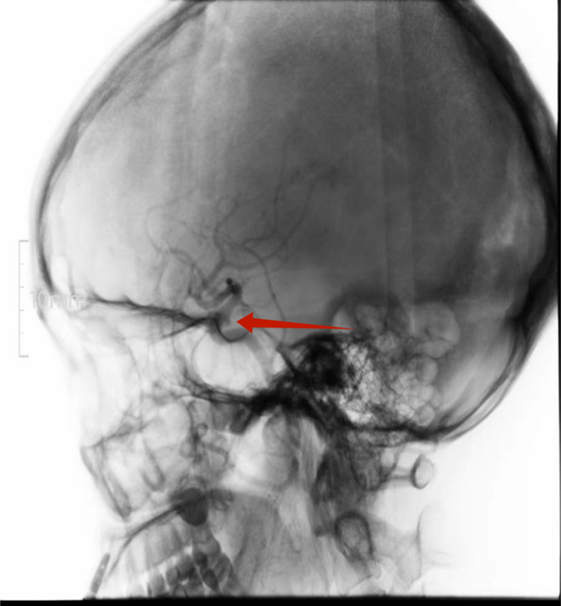

DSA证实微小动脉瘤

患者李女士,女,44岁,反复头晕2年多,在我院行头颈联合3D-TOF-MRA筛查,发现右侧颈内动脉C7段2.5mm微小动脉瘤。